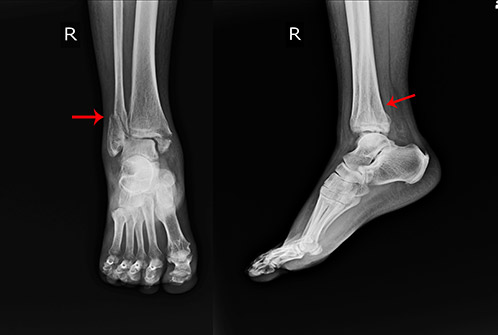

Ankle fractures

Description:

Ankle fractures occur when the bones in the ankle joint sustain a break as a consequence of an injury. Pain, swelling, bruising, tenderness and difficulty to bear weight are all common after ankle fractures.

Treatment:

The severity of the fracture as seen on an X-ray will determine the type of treatment that can range from a few weeks of leg support in a boot or surgery to fix the broken bones.